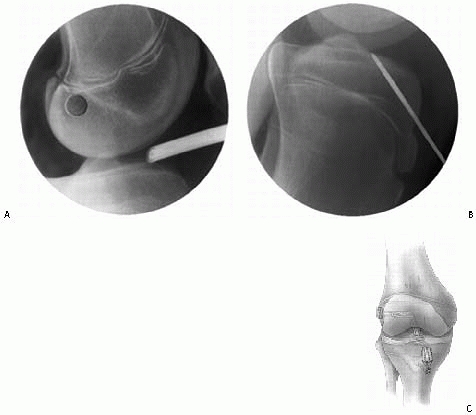

arthroscopic reduction and internal fixation. However, open reduction

through a medial parapatellar incision can also be performed per

surgeon preference/experience or if arthroscopic visualization is

difficult. The author’s preferred fixation is epiphyseal cannulated

screws if the fragment is large or suture fixation if the fragment is

small or comminuted.

positioned supine on the operating room table. A lateral breakaway post

is used. Alternatively, a circumferential post can be utilized. A

standard arthroscope is used in most patients. A small (2.7-mm)

arthroscope is used in younger children. An arthroscopic fluid pump is

used at 35 torr. A tourniquet is routinely used. Standard anteromedial

and anterolateral portals are used. Accessory superomedial and

superolateral portals are used for screw insertion. Prior to insertion

of the arthroscope through the arthroscopic cannula, the large hematoma

is evacuated.

joint, medial compartment, and lateral compartment are essential to

evaluate for concomitant injuries. Usually, some anterior fat pad must

be excised with an arthroscopic shaver for complete visualization of

the intercondylar eminence fragment. Entrapped medial meniscus or

intermeniscal ligament is extracted with an arthroscopic probe and

retracted with a retention suture (see Fig. 24-5). The base of the tibial eminence fragment is elevated (Fig. 24-9A) and the fracture bed débrided with an arthroscopic shaver and hand curette (Fig. 24-9B).

Anatomic reduction is obtained using an arthroscopic probe or

microfracture pick with the knee in 30 to 90 degrees of flexion (Fig. 24-9C).

Cannulated guidewires are placed through portals just off the

superomedial and superolateral borders of the patella. A spinal needle

can be helpful for the localization of these portals. The guidewires

are placed into the intercondylar eminence at the base of the ACL.

Fluoroscopic assistance is utilized to confirm anatomic reduction, to

guide correct wire orientation, and to avoid guidewire protrusion

across the proximal tibial physis. A cannulated drill is used over the

guidewires and one or two screws are placed based on the size of the

tibial eminence fragment (Fig. 24-9D). Partially threaded 3.5-mm diameter screws (Fig. 24-9E)

are used in children and 4.5-mm diameter screws are used in

adolescents. The knee is brought through a range of motion to ensure

rigid fixation without fracture displacement and to evaluate for

impingement of the screw heads in extension.

technique described for epiphyseal screw fixation. Accessory

superomedial and superolateral portals are not used. The fracture is

elevated (Fig. 24-11A) and the fracture base débrided (Fig. 24-11B). The fracture is reduced. A suture is passed through the base of the ACL using a suture punch (Fig. 24-11C)

or a suture passer. Two guidewires are placed using the tibial ACL

guide system from a small incision made just below the tibial tubercle.

The guidewires are placed through the base of the intercondylar

eminence fragment (Fig. 24-11D). Suture retrievers are placed through the guidewire tracts, the sutures are retrieved (Fig. 24-11E), and the sutures are tied down onto the tibia (Fig. 24-11F).

The procedure may be repeated for additional sutures. Heavy

nonabsorbable braided sutures or fiberwire is used. Although these

sutures traverse the proximal tibial physis, the risk of growth

disturbance is minimal given the small diameter of the guide wire holes.

![]() |

|

FIGURE 24-9 Arthroscopic reduction and cannulated screw internal fixation of a displaced tibial spine fracture. A. Elevation of the tibial eminence fragment. B. Débridement of the fracture bed. C. Reduction of the tibial eminence. D. Drilling over the cannulated screw guidewire. E. Cannulated screw fixation.